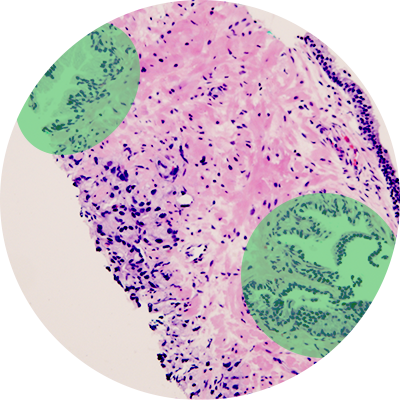

The method is called molecular preservation by extraction and fixation (mPREF). In a proof-of-principle study, researchers used the method to study 25 samples from patients undergoing a prostatectomy. They found that 2,900 metabolites were consistently detected in more than 50 percent of the samples. This unprecedented coverage helped identify significant metabolites for differentiating tumor and normal tissues.

“Our long-term goal of using mPREF in prostate cancer is to identify metabolite biomarkers that are prognostic,” says Dean Troyer, MD, Professor of Microbiology and Molecular Cell Biology, Associate Director of Translational Research at the EVMS Leroy T. Canoles Jr. Cancer Research Center and co-lead author of the study. “This method offers a powerful and convenient means of performing histopathology and discovering or detecting metabolite biomarkers in the same tissue biopsy.”